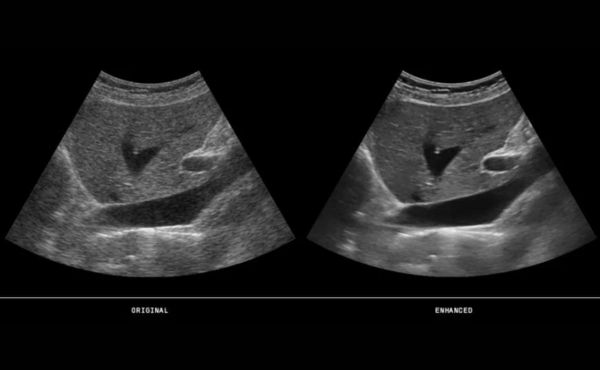

Badania obrazowe, takie jak ultrasonografia (USG), tomografia komputerowa (TK) i rezonans magnetyczny (RM) są wykorzystywane do wykrywania nowotworów wątroby.

- USG może być często wykonywane jako pierwsze badanie, ponieważ jest powszechnie dostępne i nieinwazyjne. Może pomóc w wykryciu guzów oraz ocenie struktury wątroby i przepływu krwi.

- TK i RM dostarczają bardziej szczegółowych obrazów anatomicznych i mogą być używane do oceny stopnia zaawansowania nowotworu.